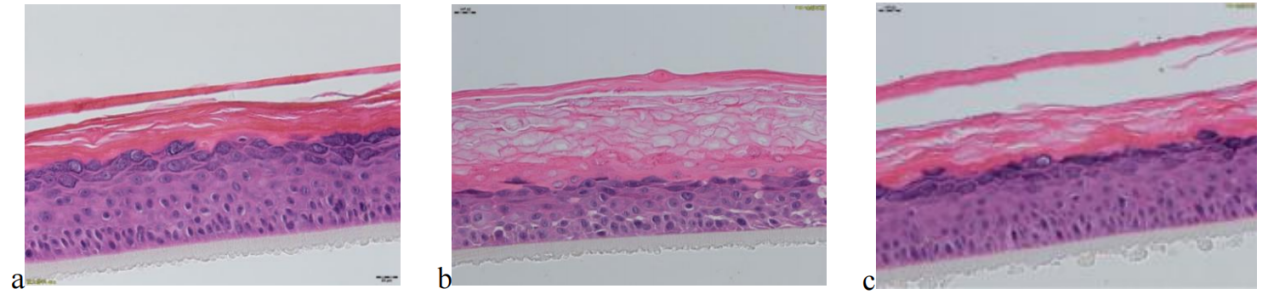

待測(cè)活性物與BAP聯(lián)合作用于EpiKutis® 皮膚模型后,形態(tài)學(xué)結(jié)果見(jiàn)圖6。與空白對(duì)照組(Control)相比,刺激組(BAP)的角質(zhì)層增厚、排列疏松、空泡明顯且分化不完全;活細(xì)胞層(顆粒層、棘層、基底層)活細(xì)胞數(shù)目減少,基底層細(xì)胞空泡明顯,排列疏散。

圖 6 不同處理?xiàng)l件下表皮模型的形態(tài)學(xué)變化情況(放大40倍)

(a.空白對(duì)照組,b.BAP刺激組,c.待測(cè)活性物組)